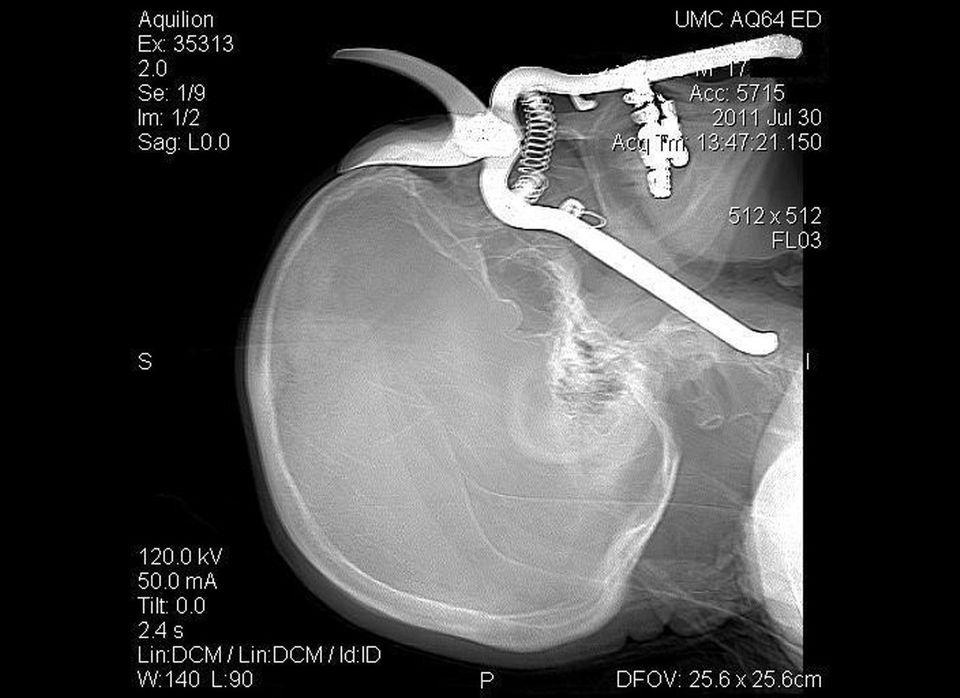

Một khẩu súng bắn đinh đã găm 6 chiếc đinh vào sọ não công nhân xây dựng Isidro Mejia trong một tai nạn vào tháng 4/2004 . May mắn là người công nhân này đã sống sót và phục hồi sau đó.